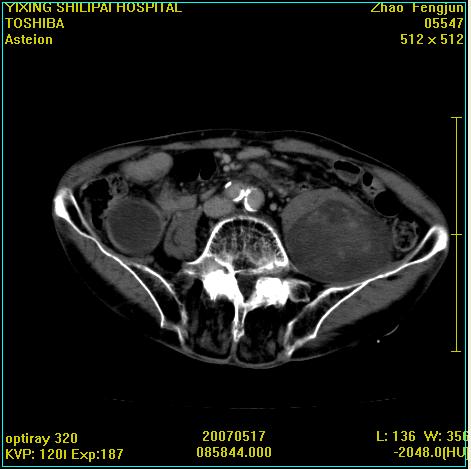

考虑:1、左侧腰大肌囊实性占位性病变(囊性神经根鞘瘤?);

2、右侧兰尾区囊性占位性病变(兰尾囊肿?囊腺癌?类癌?)

以下是引用xiaoniu在2007-5-26 10:45:00的发言:[br]腰大肌的病变应该没有问题,增强扫描还有轻度强化及细小血管影入内,应该排除脓肿,考虑占位性病变,腰大肌的占位多考虑:神经源性肿瘤。另外腹主动脉下端有真假腔的强化,考虑:主动脉夹层。[br][br][本贴已被 xiaoniu 于 2007-5-26 10:46:39 修改过]

以下是引用老爱克斯新网客在2007-5-26 18:26:00的发言:[br]1左下腹囊实性占位肿块,增强后不均匀强化,位于脊柱旁,椎体骨质无破坏软组织无肿胀,考虑神经源肿瘤神经鞘瘤可能大,2右下腹囊性占位性病变,增强后囊壁强化,考虑阑尾囊肿或囊腺瘤,